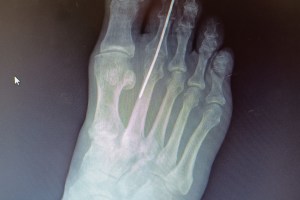

Hammer-toe Time Again: Surgery and Convalescence Six Weeks In